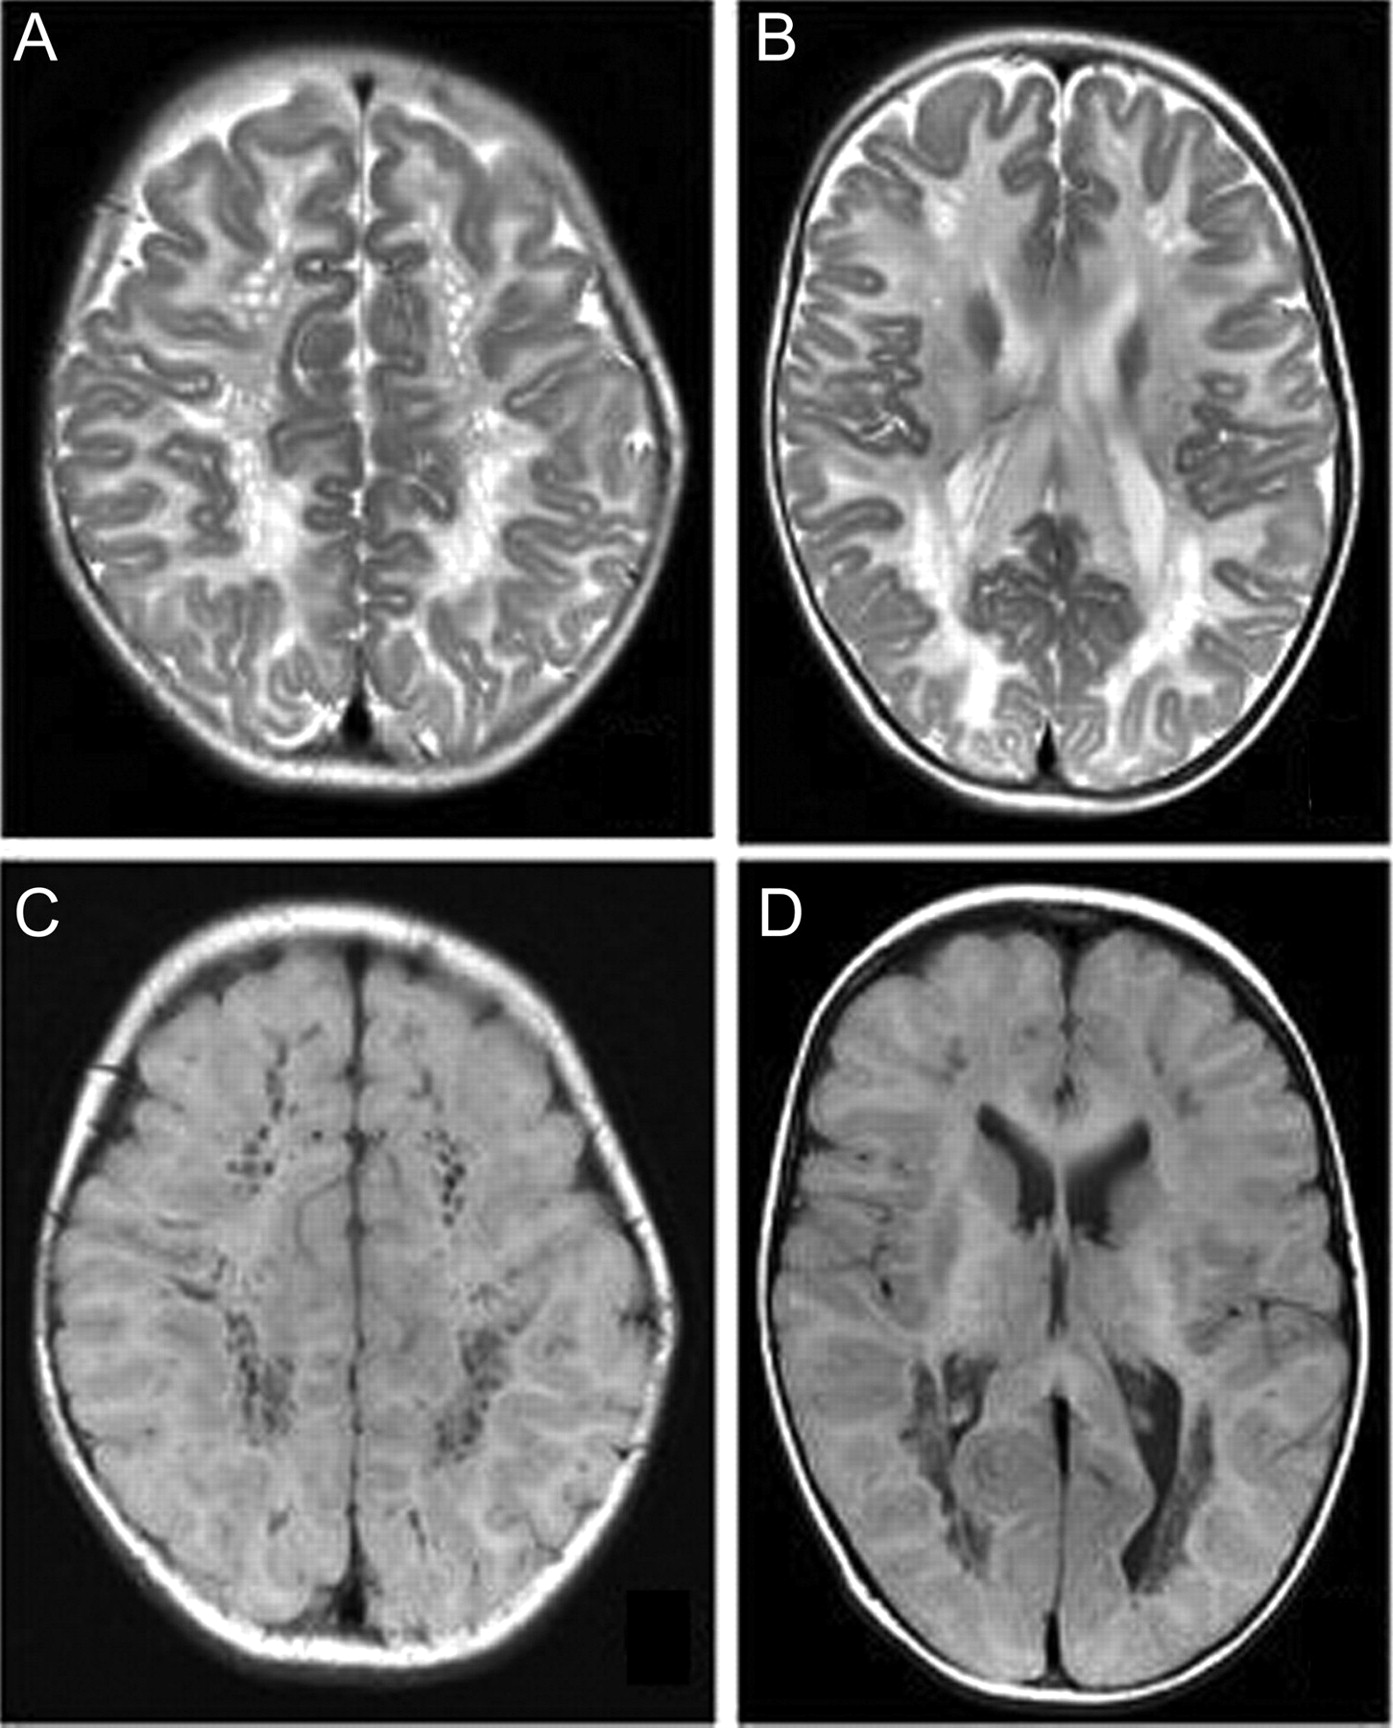

图1

脑部核磁共振成像

T2加权(A, B)和T1 (C, D)大脑的核磁共振显示严重和扩散T2 hyperintense和T1 hypointense白质信号变化表明Canavan疾病。U纤维存在的重要参与。白质内多个圆形或椭圆形囊性改变蜂窝的外表。这些囊性空间的径向排列表明Virchow-Robin空间的扩张由于海绵状白质变性。